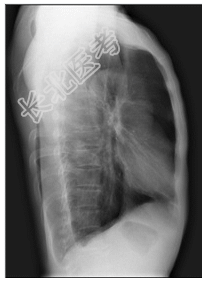

- [材料题] 患者,男性,70岁,秋冬季咳嗽、咳痰3年余,胸闷、气促2天入院。查体:桶状胸,双肺呼吸音粗,未闻及干、湿性啰音。心脏体查无异常。做胸部X光平片检查。

- 简答题1、诊断及依据是什么?

- 简答题2、鉴别诊断有哪些?